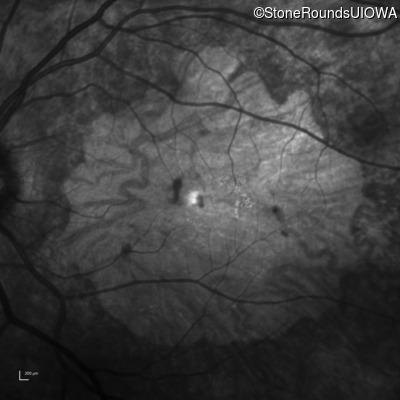

Infrared Fundus Photograph - Left - 20/250 sc

Exemplar